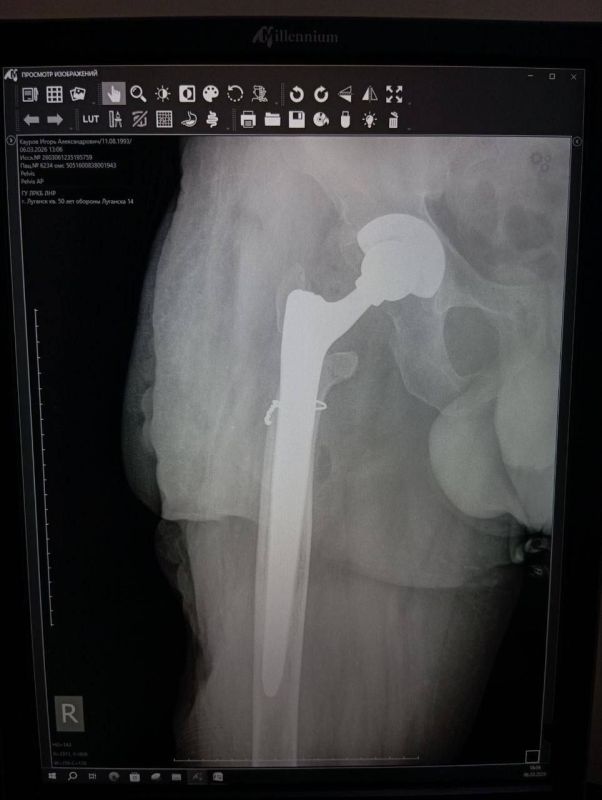

Об этом сообщила министр здравоохранения ЛНР Наталия Пащенко.Руководитель Минздрава рассказала, что борьба сержанта из ЛНР, мужчины 1993 года рождения, длилась три с половиной года. За это время он проходил лечение в десяти госпиталях, в том числе в...

Уникальная операция в Луганской республиканской клинической больнице вернула ветерану специальной военной операции (СВО) возможность ходить без хромоты. Об этом сообщила министр здравоохранения ЛНР Наталия Пащенко. Руководитель Минздрава...

Об этом сообщила министр здравоохранения ЛНР Наталия Пащенко в своем телеграм-канале.Боец ушел на фронт 25 февраля 2022 года, прошел через горнило Херсонщины, а тяжелое ранение получил 28 августа.«Из-за обширных повреждений и многократных операций...